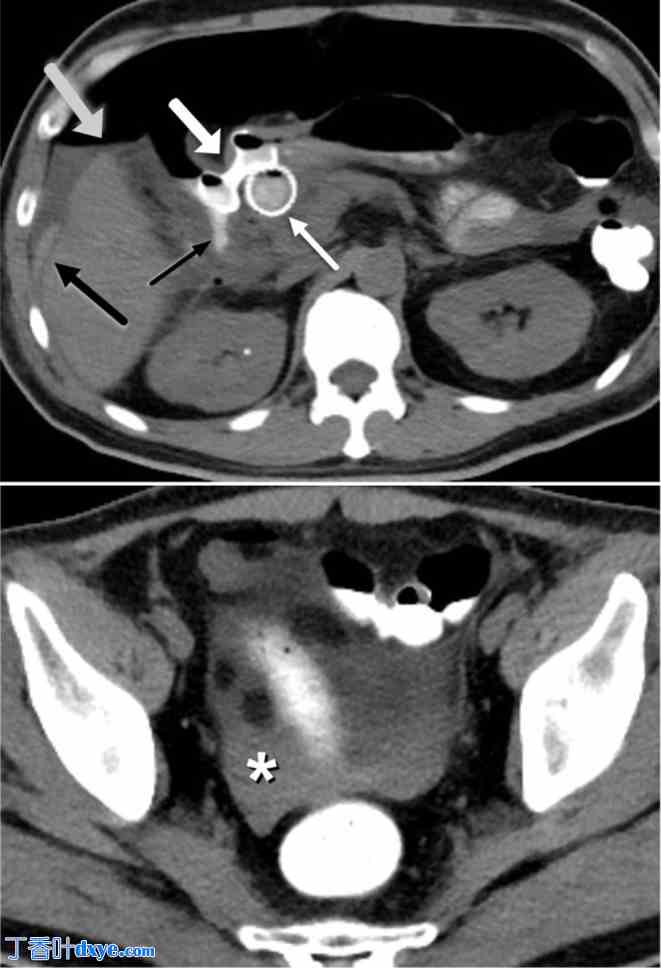

图 8。

8.jpg

83 岁男性,胰腺癌患者,接受姑息性内镜胃空肠造口术。A. 造影剂增强轴向 CT 图像显示部分胃出口阻塞,由于已知幽门和十二指肠第一部分存在胰腺癌(白色箭头),胃膨胀,充满口服造影剂(黑色箭头)。B. 造影剂增强冠状 CT 图像显示通过 LAMS 进行姑息性胃空肠造口术(白色星号),显示管腔通畅,可缓解阻塞并避免手术

图 10。

10.jpg

26 岁女性出现输卵管卵巢脓肿破裂,无法通过 IR 引流进入。A. 对比增强轴向 CT 图像显示输卵管卵巢脓肿破裂(白色星号)。B. 对比增强轴向 CT 图像显示通过 LAMS(黑色箭头)成功间歇性引流到直肠(黑色星号)